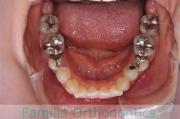

歯並びを治したいということで来院されました。下あごがやや右側に偏位して後退している、上顎前突(出っ歯)でした。上下左右から小臼歯を抜歯して、歯科矯正用アンカースクリューを併用したマルチブラケット法にて治療を行いました。約2年、24回の来院をしていただきました。

下顎の後退はいびきなどの上部気道の障害が出やすいと考えられます。